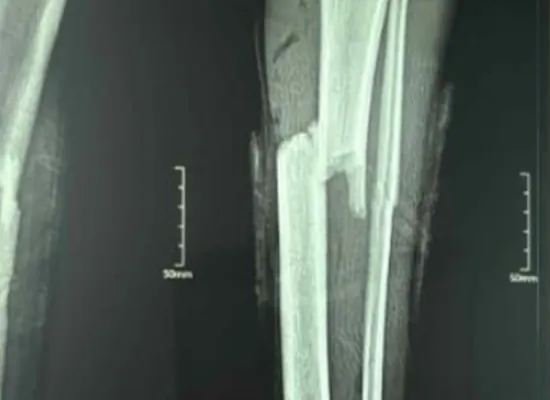

Imazhi para operacionit zbuloi një frakturë tibiale të boshtit të mesit me zhvendosje të lehtë. Një teknikë hibride e fiksimit (gozhdë + pllakë) u zgjodh për të rritur forcën mekanike dhe për të promovuar rikuperimin e sigurt.

Preoperative X-ray e frakturës tibiale

Radiografitë postoperative treguan shtrirje të shkëlqyer dhe integritet të fiksimit. Pacienti filloi rehabilitimin e butë brenda javësh dhe arriti ecje pa dhimbje menjëherë pas kësaj.

X-ray postoperator që tregon shërim